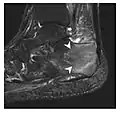

High-energy trauma fractures

Occult osseous injuries may result from a direct blow to the bone by compressive forces of adjacent bones against one another or by traction forces during an avulsion injury. Lesions in the tibial plateau, hip, ankle, and wrist are often missed. In a tibial plateau fracture, any disruption of the posterior and anterior cortical rims of the plateau should be sought. Impaction of subchondral bone will appear as an increased sclerosis of the subchondral bone (Figure 1). In the hip, posterior acetabular fractures also present subtle radiographic findings. The acetabular lines should then be carefully examined keeping in mind that the posterior rim, which is harder to see on X-rays, is more frequently fractured than the anterior rim (Figure 2). In the wrist, detection of carpal bone fractures is often challenging, with up to 18% of scaphoid fractures radiographically occult. Carpal fractures, especially the scaphoid, are associated with the risk of avascular necrosis. In apparently normal wrist radiographs from symptomatic patients, if there is history of a fall on an outstretched hand with pain in the anatomic snuffbox, suggesting scaphoid injury, the initial examination with posteroanterior, lateral, and pronation oblique views must be complemented by other specific views such as supination oblique and the "scaphoid" view A careful examination of cortices for evidence of discontinuity or offset and cancellous bone for lucency is necessary (Figure 3).[1]

a

b

c

Figure 1: A 56-year-old woman presenting with left knee pain after a fall. (a) Initial anteroposterior radiograph was considered normal, however, subtle cortical disruption of the anterior rim of the medial tibial plateau, medial to the tibial spine, is noted (arrow). (b) Coronal T1-weighted MRI confirms the cortical disruption (arrow) and shows extensive fracture through the proximal tibia. (c) Coronal proton density-weighted image with fat saturation shows extensive edema in the subchondral bone. Note also hypersignal adjacent to the medial collateral ligament corresponding to a grade I sprain (arrowheads).[1]